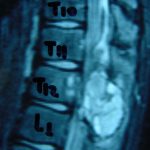

Εικ. 3: Μαγνητική τομογραφία α-στ Οβελιαία (Saggital) λήψη ακολουθία Τ1-Τ2, ζ-ιβ Εγκάρσια (Axial) λήψη ακολουθία Τ1-Τ2

Παρατηρείται ευμεγέθης εξεργασία στα οπίσθια στοιχεία του Θ12 σπονδύλου η οποία προκαλεί διόγκωση των δομών , λέπτυνση του φλοιού, χωρίς σημάδια διάσπασης του φλοιού. Η εξεργασία προβάλλει και στενεύει το σπονδυλικό σωλήνα, ενώ προκαλεί πίεση του νωτιαίου μυελού. Δεν αναγνωρίστηκαν παθολογικά ευρήματα από τον έλεγχο των σπονδυλικών σωμάτων και των μεσοσπονδύλιων τμημάτων της ΟΜΣΣ.